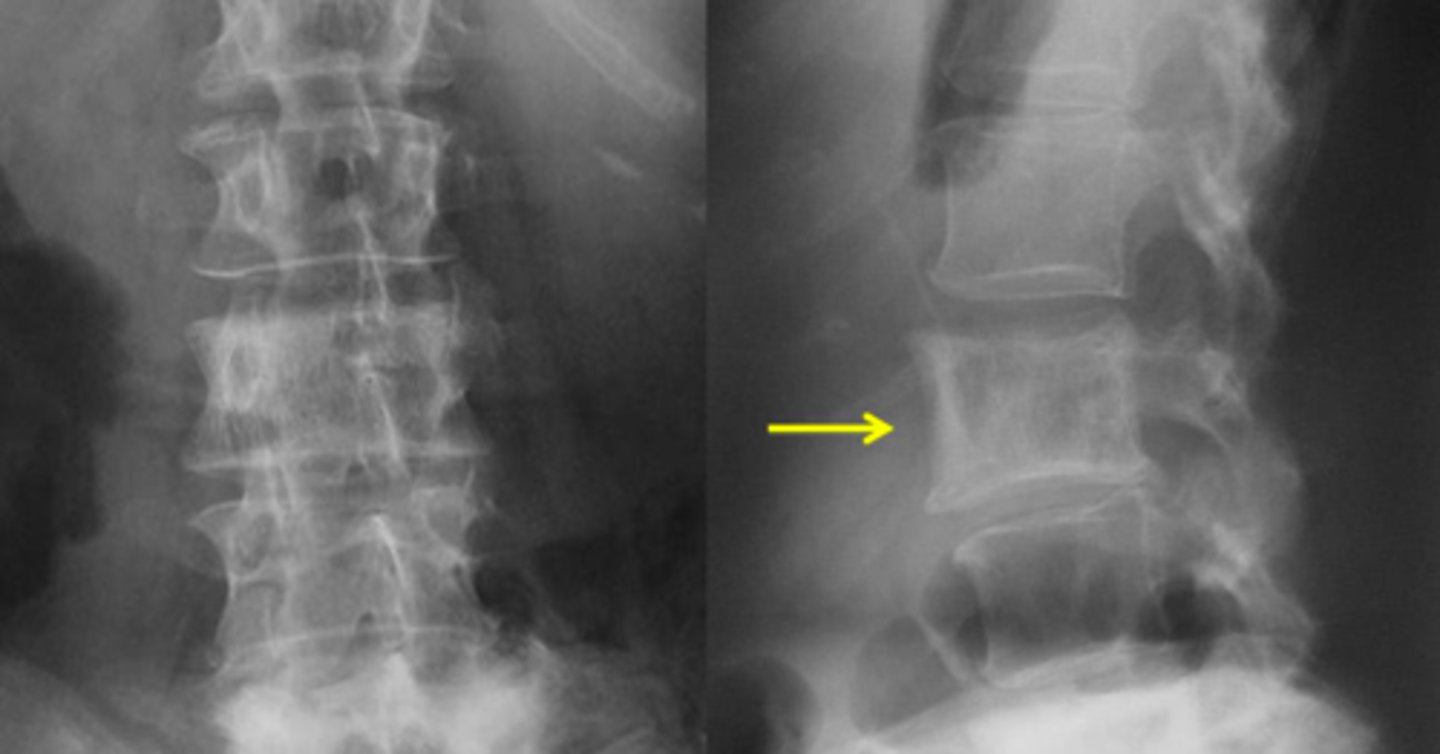

Vignette #1:

Sex: Male

Age: 62

Chief Complaint: Patient presents with low back pain and initiating urinary streams. He reports polyuria in the middle of the night.

Objective Findings: Kemps + Diagnostic Imaging: X-ray

Which labs would you expect to be positive? (Choose 3)

a. PSA

b. Acid phosphatase

c. Alkaline phosphatase

d. ESR

e. CRP

f. Proteinuria

g. BUN

h. Biopsy for Reed Sternberg

What are your differential diagnoses? (Choose 3)

a. Paget's

b. BPH

c. Osteomyelitis

d. Multiple Myeloma

e. Blastic Metastasis

f. Hodgkin's Disease

g. Lytic Metastasis